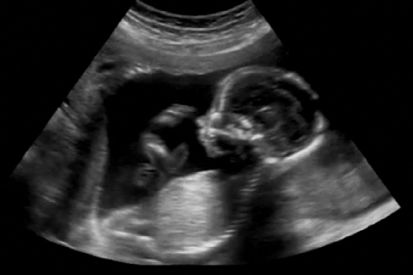

Zwangerschap Heb jij je zwangerschap ontdekt bij 30 weken of later? Dan interviewt Fiom je graag! Chantal 30 april